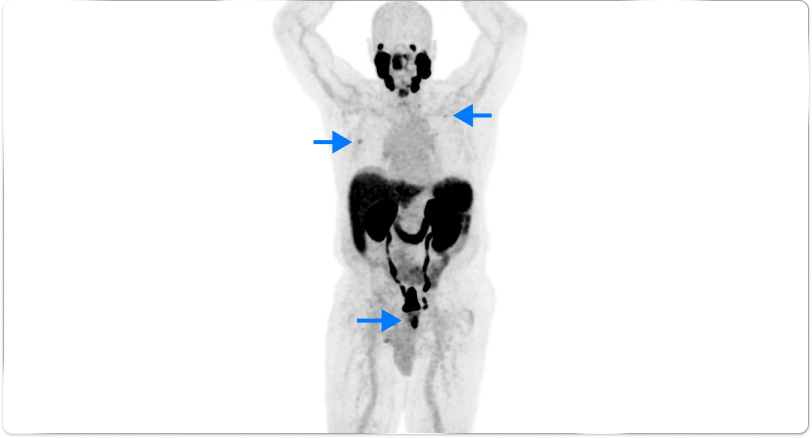

High-risk patient with newly diagnosed prostate cancer

Age

72

PSA (ng/mL)

5.1

Gleason Score

4 + 4

PYLARIFY prompted treatment change from prostatectomy to systemic therapy, thereby avoiding undertreatment